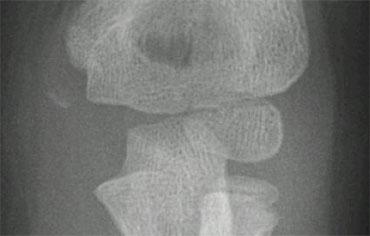

On AP-view the avulsed medial epicondyle projects over the trochlea. Lateral view shows the fragment to be trapped within the joint.

Avulsion mỏm trên lồi cầu trong (5).

Một mảnh xương bị avulsion nằm trong khớp có thể gây khó khăn trong chẩn đoán.

Trên phim thẳng AP, mảnh xương này có thể bị bỏ sót (hình).

Khi ròng rọc chưa được cốt hóa, mảnh avulsion có thể giả dạng trung tâm cốt hóa của ròng rọc.